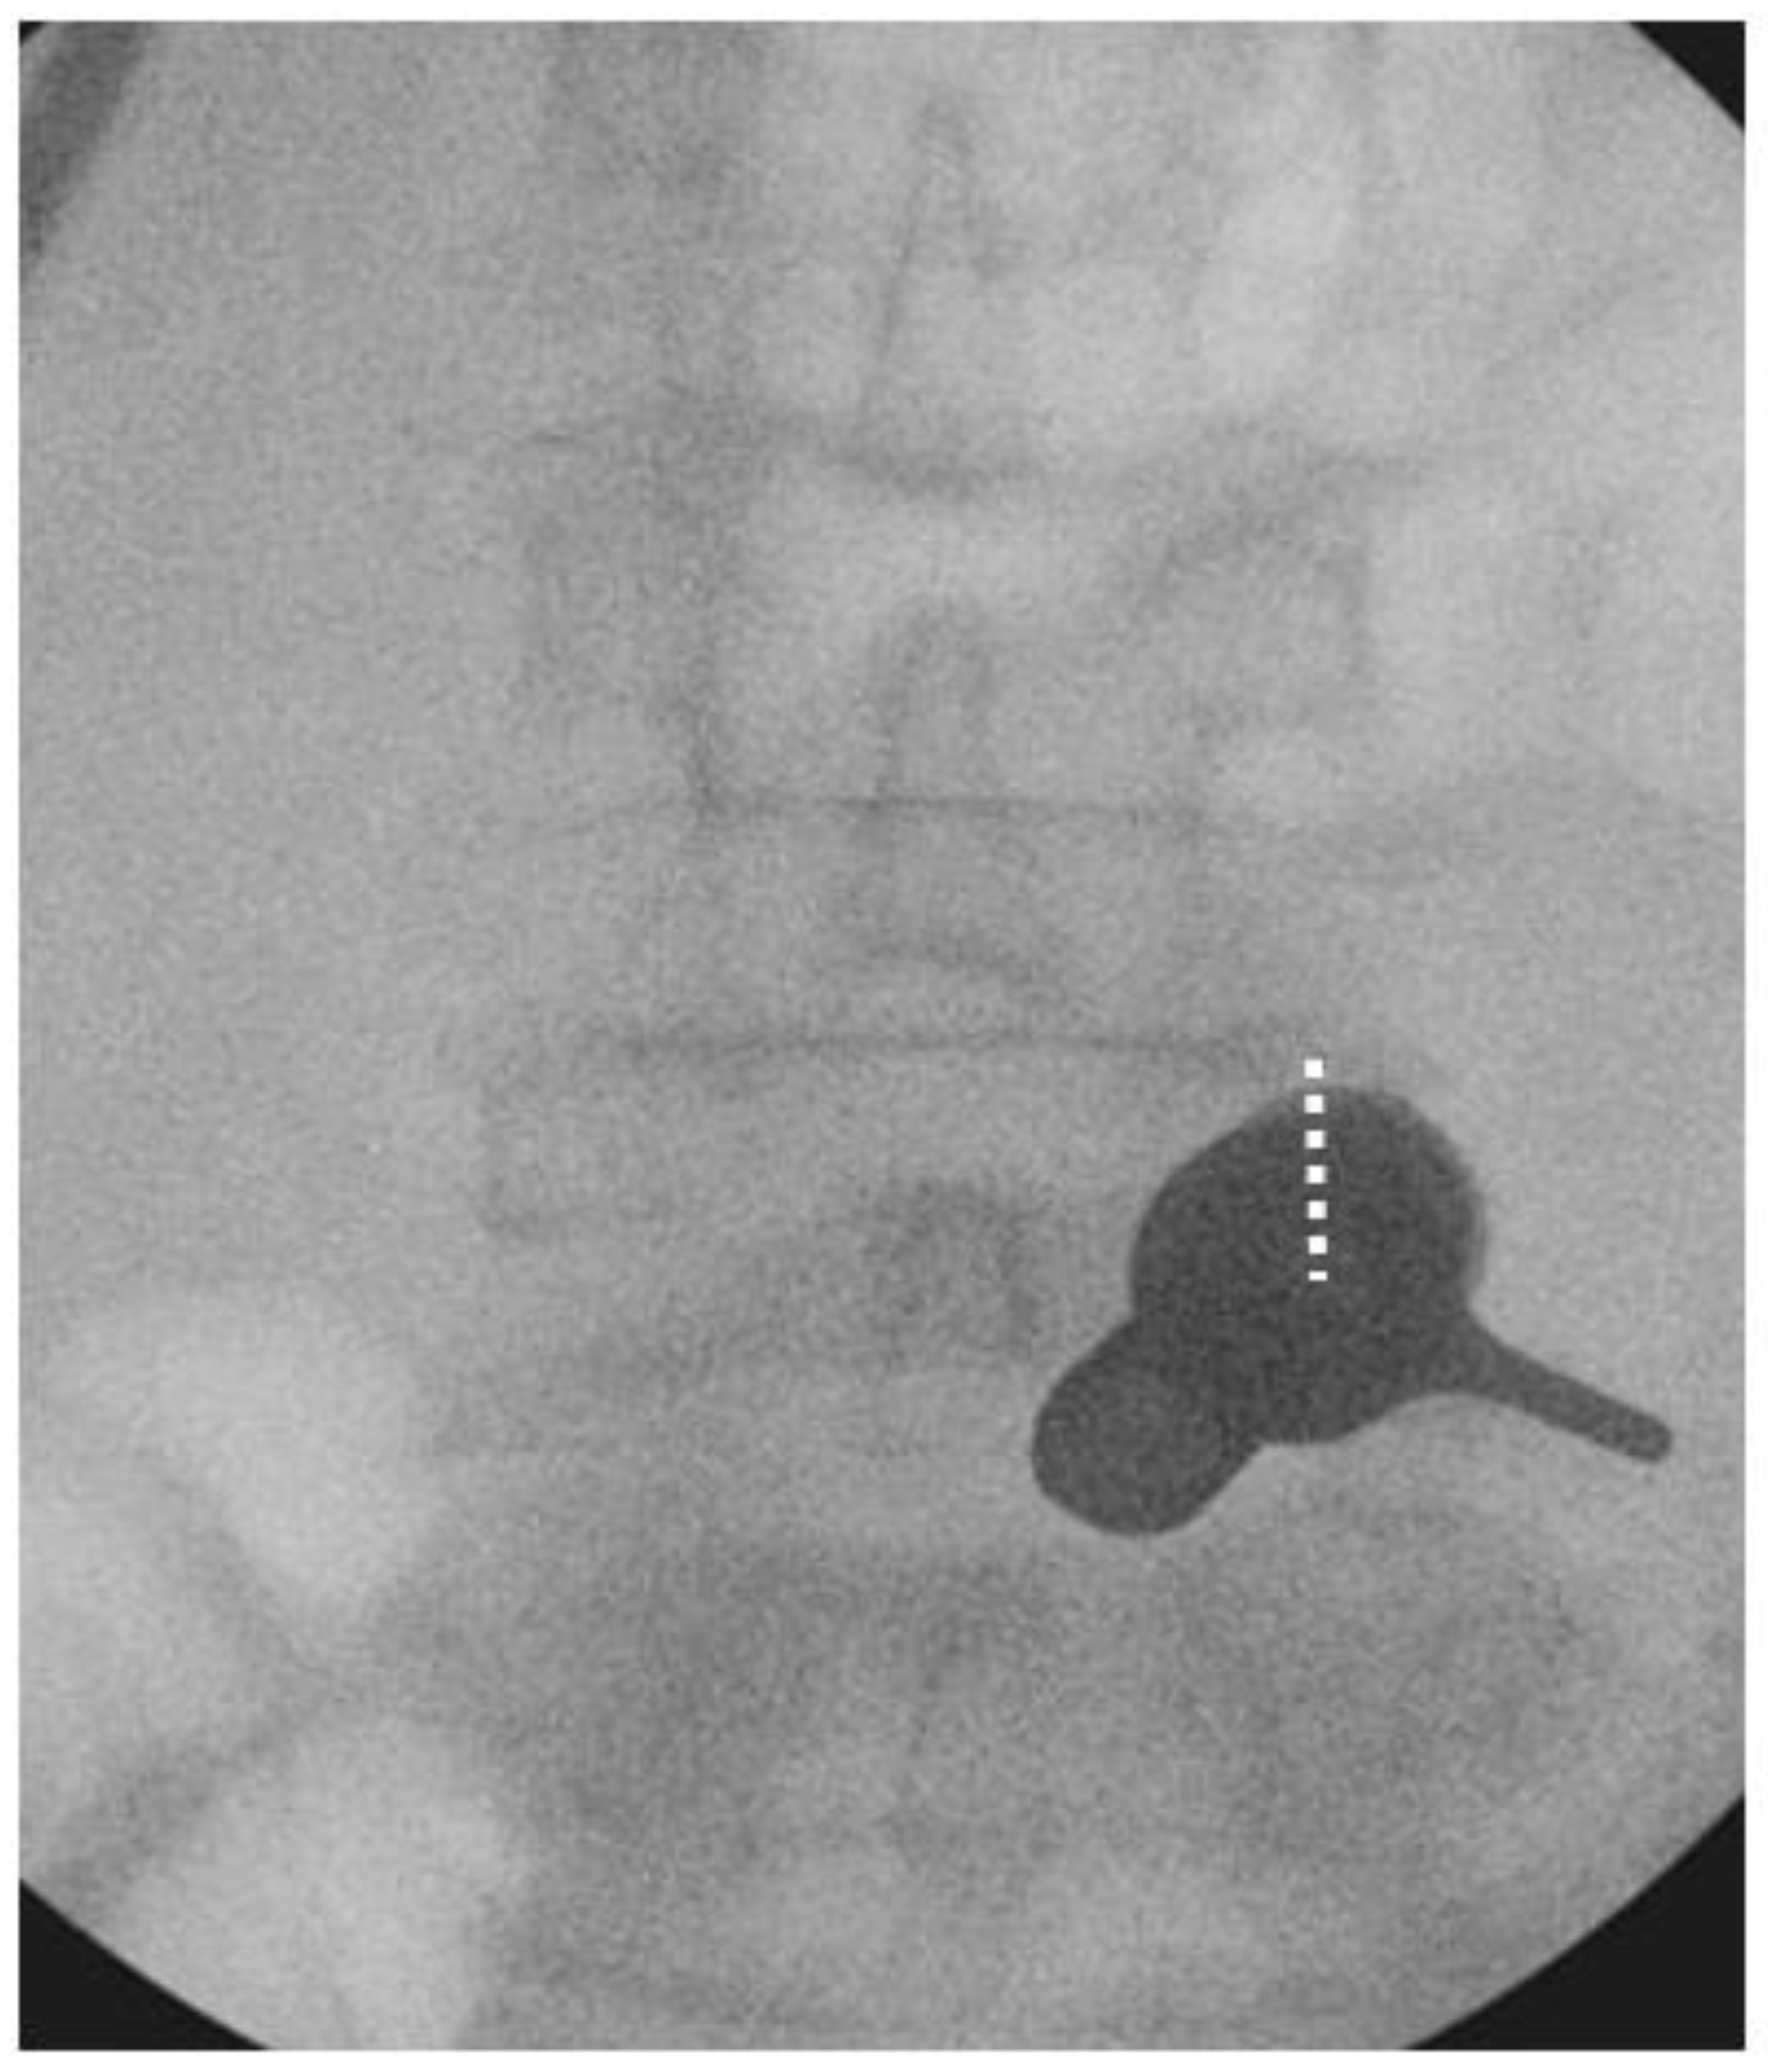

We performed the procedure under general anesthesia. The patient was positioned in a prone position on a Wilson Frame over a radiolucent operating table with the spine in slight flexion. The endoscopic procedure was performed with an irrigation fluid pressure of 25–40 mmHg using an irrigation pump. We stood on the symptomatic side and used the upper pedicle screw skin incision for the uniportal endoscope insertion and docking for each corresponding level of posterolateral approach interbody fusion. For example, we used the skin incision over the right L4 pedicle on the AP intraoperative fluoroscopic image to perform right L4/5 Endo-TLIF (Figure 5) We incised a 1.6 cm skin incision to facilitate working cannula placement and made an extended fascia incision of 3 cm to allow mobility of the working channel and subsequent rod placement after completion of interbody cage insertion. We performed the insertion of the cage(s) prior to pedicle screw insertion.

Figure 5. Docking position of right L4/5 Endo-TLIF. The incision was made over the right L4 pedicle (dotted white line) and the working cannula was docked on the pars interarticularlis of right L4/5.